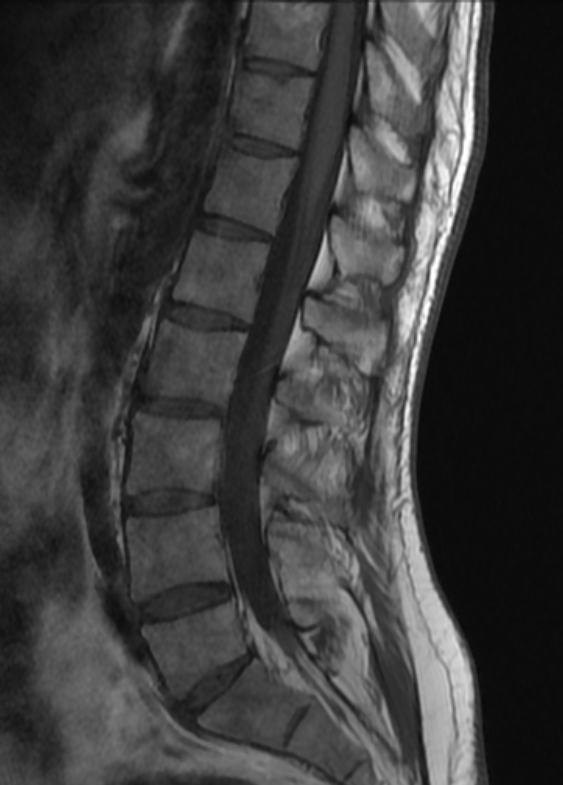

70y/o👩🏾‍🦳.Expansile lession w/mild mass effect on the conus medullaris&cauda equina. Scalloping of the posterior elements. HighT2 signal No DWI anomaly. Most likely spinal(apparently)extradural arachnoid cyst. Same date brain MR:no brain sag nor congestion #spinerad @The_ASSR

josealejandrobv's tweet image. 70y/o👩🏾‍🦳.Expansile lession w/mild mass effect on the conus medullaris&cauda equina. Scalloping of the posterior elements. HighT2 signal No DWI anomaly. Most likely spinal(apparently)extradural arachnoid cyst. Same date brain MR:no brain sag nor congestion #spinerad @The_ASSR